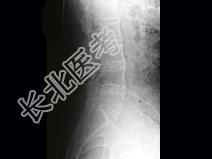

- 单项选择题男,41岁, 腰部酸肿不适10多年,近年加重, 腰部活动受限,晨僵1年, 腰椎正侧位片如图,最可能的诊断是 ( )